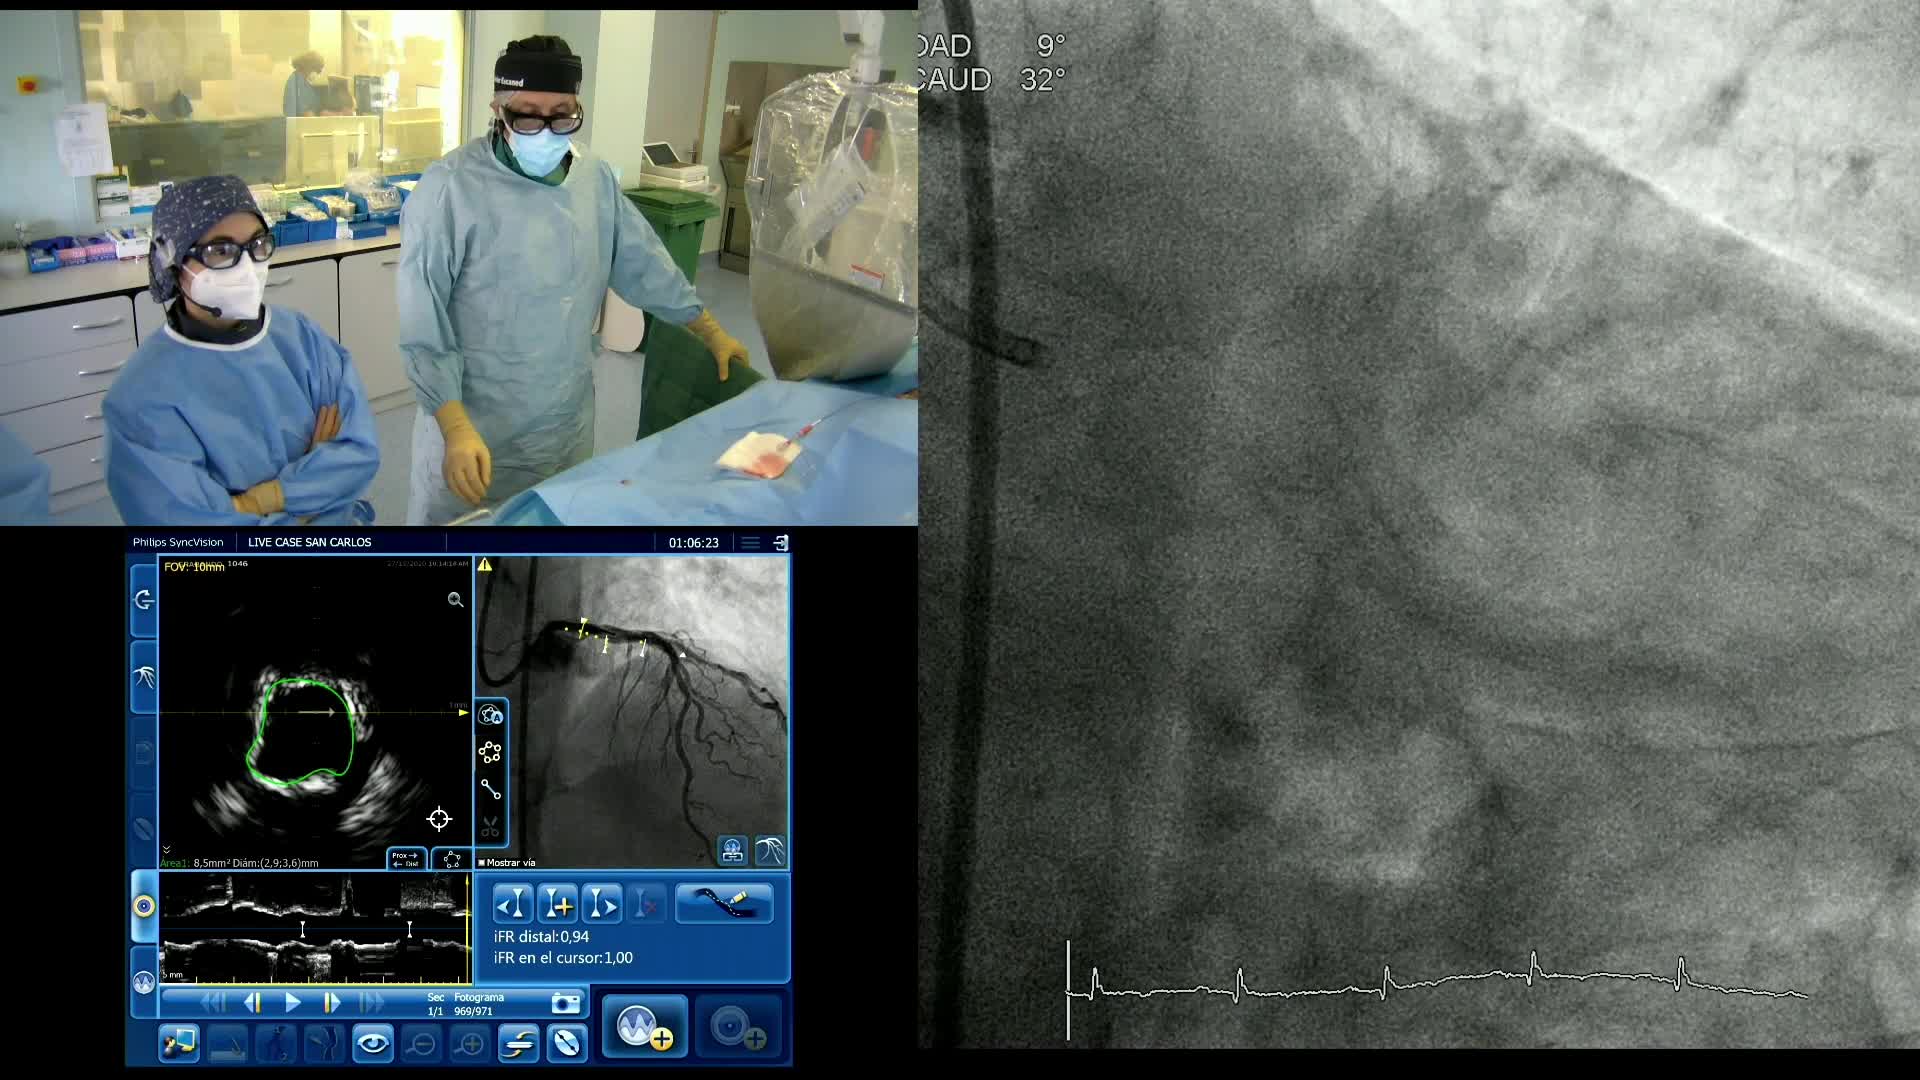

Complex PCI eCourse Madrid 26th October 2020

Complex PCI eCourse Madrid 27th October 2020

Coronary Bifurcations: An Update on Diagnosis, PCI planning and Imaging and PhysiologyGuidance - Dr Dejan Milasinovic